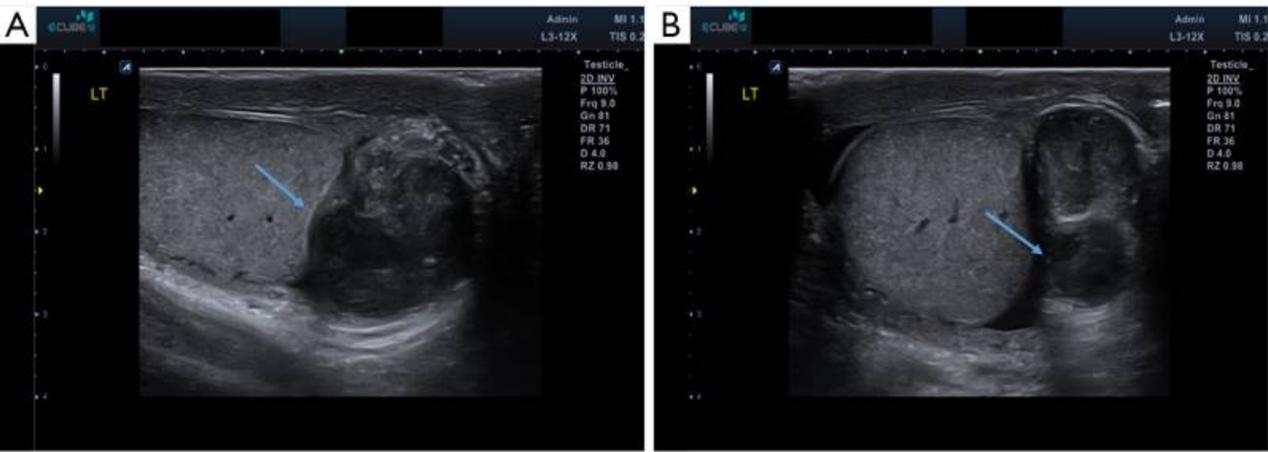

阴囊超声显示左侧附睾严重扩张,回声不均匀,左侧附睾附近有不规则形态的液体,提示严重附睾炎伴脓肿形成,睾丸未见异常(图1)。右侧睾丸和附睾正常(图1)。血液中的睾丸肿瘤标志物,如甲胎蛋白、人绒毛膜促性腺激素和乳酸脱氢酶,结果在正常范围内。

图1 附睾结核患者的阴囊超声图像。(A,B)左侧附睾严重扩张,回声不均匀(蓝色箭头),不规则形状的液体填充,提示形成脓肿的严重附睾炎